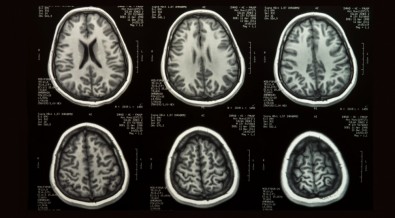

Um grupo internacional de cientistas, incluindo brasileiros, reuniu 123.984 exames de ressonância magnética para mapear o desenvolvimento do cérebro humano desde as primeiras semanas do feto até os 100 anos de idade. Com esse banco, foram montados gráficos que mostram a evolução cerebral ao longo dos anos, incluindo fases de rápida expansão no início da vida e de redução do tamanho do órgão durante o envelhecimento.